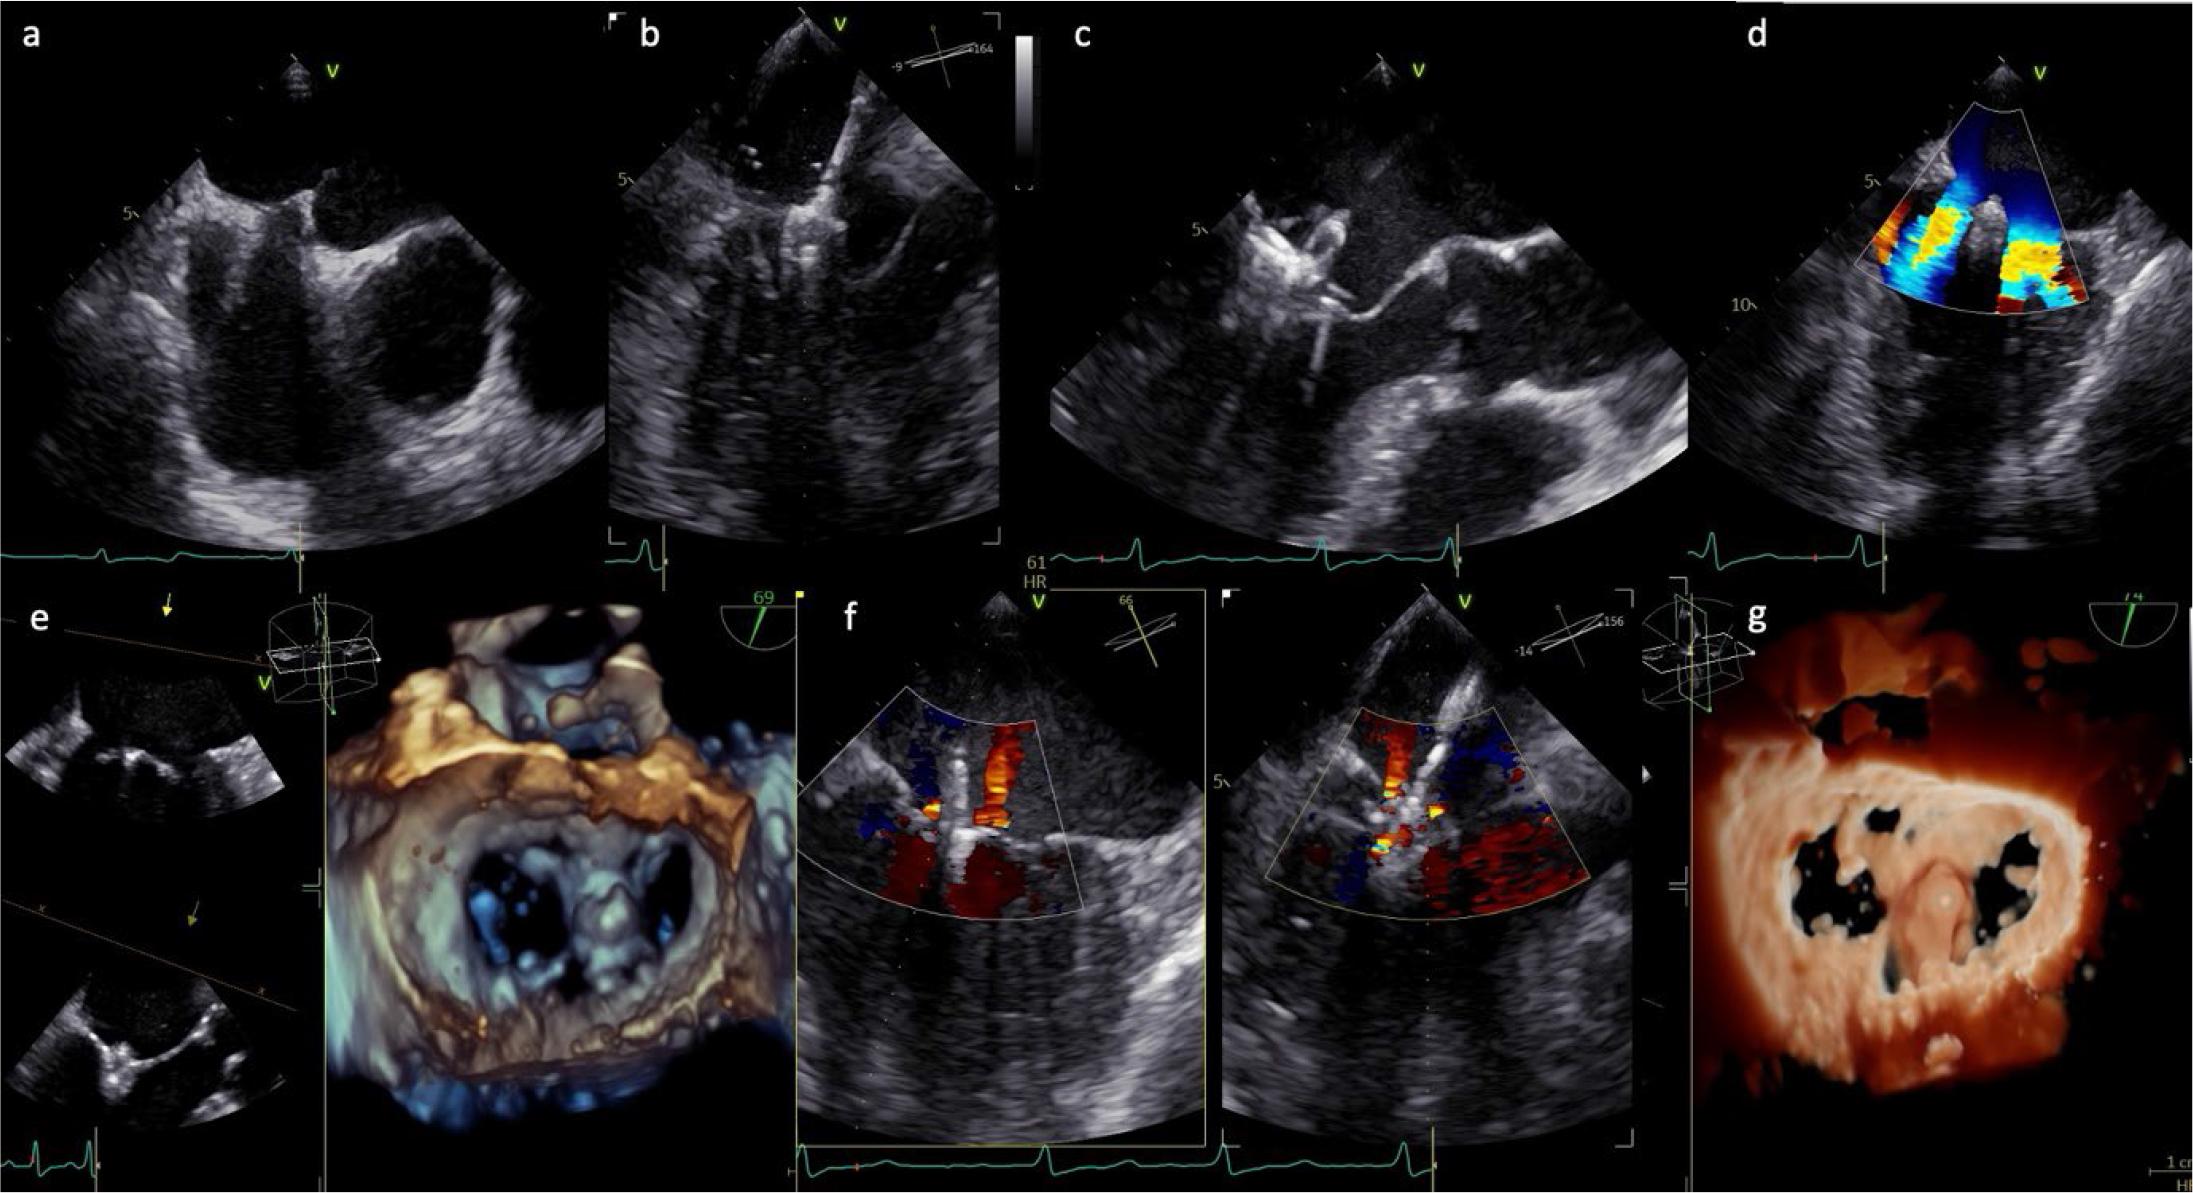

Both PASCAL and MitraClip procedures rely on high-quality intraprocedural imaging—chiefly TOE with 3D MPR and single-plane fluoroscopy—to guide transseptal access, device steering, leaflet grasping, and clip deployment. The use of biplane TOE during transseptal puncture provides excellent spatial orientation and has largely eliminated the routine need for biplane fluoroscopic imaging, which is now reserved for select anatomically challenging cases. Precise coordination between the imaging specialist and the interventional cardiologist is critical to ensure spatial alignment and effective device delivery.

Optimal trans-septal puncture is performed under TOE guidance, typically in a posterior-superior position, at least 4 cm above the mitral annulus to ensure a favorable trajectory for clip delivery. The procedure begins with a bicaval view (90°–120°) using an X-plane to localize and adjust the needle tip in the antero-posterior plane (Figure 4). Fusion technology allows these 2D views to be overlaid on fluoroscopy, and in recent advancements, full 3D heart segmentation can identify the optimal puncture zone. After securing LA access, the guide catheter is advanced into the left atrium. Following successful septum crossing, the position of the curved stiff wire in the left pulmonary veins (typically the left upper) or left atrium is confirmed. Fusion imaging aids in guiding this step and steering the catheter toward the mitral plane (Figure 4), avoiding interaction with the left pulmonary veins and LA appendage.[73]

Intraprocedural TOE guidance during TEER for SMR. (a) Transseptal puncture in the aortic valve short-axis view (45°); (b) advancement and steering of the catheter towards the mitral plane; (c) catheter orientation perpendicular to the mitral plane, followed by valve crossing and leaflet grasping; (d), (f) device positioned above the mitral annulus, perpendicular to the leaflet coaptation line, typically at the origin of the regurgitant jet, which is reduced after device deployment; (e), (g) 3D reconstruction of the mitral valve, en face (surgical) view, after device deployment.

The grasping view is, by definition, a targeted long-axis image at the intended landing zone that simultaneously displays the anterior and posterior leaflets for optimal capture. The commissural view is used primarily for jet localization and medial–lateral orientation, whereas precise leaflet grasping is performed in a dedicated long-axis plane.

Precise clip placement during mitral M-TEER is critical, starting with positioning the device above the mitral annulus, perpendicular to the leaflet coaptation line, typically at the regurgitant jet’s origin (Figure 4). Device orientation is guided using a 3D TOE view from the left atrium in the standardized “surgeon’s view,” with the aorta positioned at 12 o’clock. This orientation allows intuitive alignment of device movements with the intercommissural plane during steering and implantation.[73] Effective collaboration between the cardiac imaging specialist and structural interventionalist is vital, requiring a shared understanding of 3D mitral anatomy and integration of fluoroscopic and echocardiographic imaging for real-time guidance. After confirming perpendicular orientation via 3D echocardiography, adjusting the X-ray gantry angle ensures consistent device alignment during fluoroscopy-guided grasping.

For valve crossing and leaflet grasping, standardized views are employed, including an intercommissural view (50°–70°) with an X-plane to obtain a LVLVOT view (140°–160°) of the A2/P2 segment, displaying both leaflets clearly Figure 4).[73] Simultaneous visualization of these planes allows trajectory corrections, ensuring the catheter remains in the left ventricle to facilitate grasping and prevent valve distortion. Catheter adjustments—pulling/pushing, flexing/unflexing, or rotating clockwise/counterclockwise—shift the device medially/laterally or toward the posterior/anterior, respectively, as seen in the intercommissural and LVOT views. Flexing the guide sheath corrects an “aorta-hugger” position or adjusts height, while posterior rotation increases height. For commissural pathologies, the intercommissural plane is adjusted to 30°–60° for A3/P3 or 60°–90° for A1/P1 to align with the coaptation line, with optimal views derived from 3D MPRs.[73]

Once aligned, the clip arms are opened perpendicular to the coaptation plane. Depending on the operator’s preference, the device may advance into the left ventricle with arms open or closed, with open-arm advancement requiring intraprocedural orientation adjustments (Figure 4). Before grasping, both mitral leaflets must be confirmed as freely mobile above the open clip arms, precisely positioned along the coaptation line.[73] Grippers are then deployed to secure the leaflets between the clip arms and grippers, with partial clip closure confirming initial leaflet capture (Figure 4).